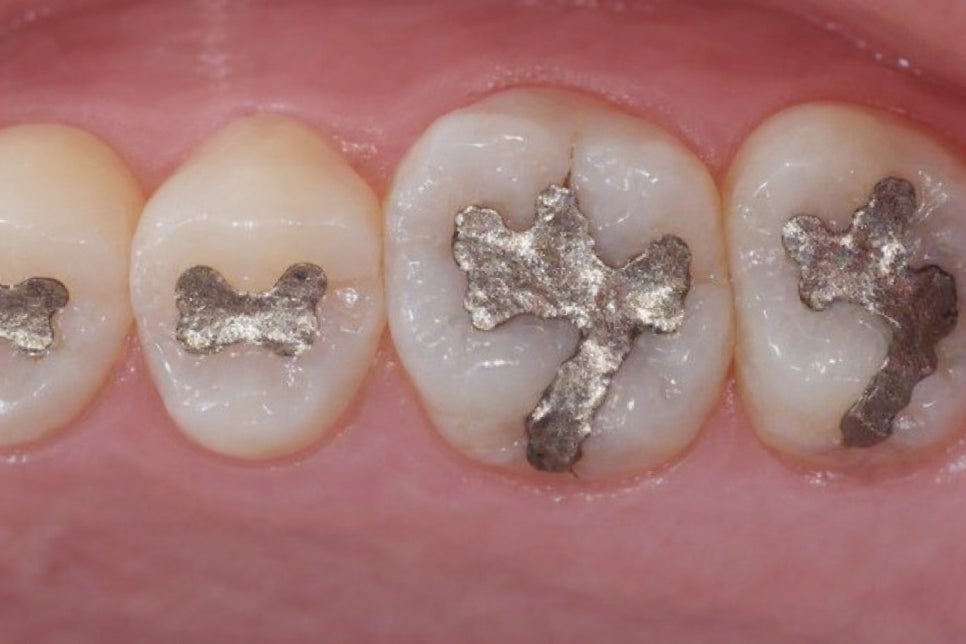

🔻 오래된 아말감 충전재가 있는 경우에도

온도 변화에 따른 팽창과 수축이 반복하면서

미세한 crack이 발생할 수 있습니다.

아말감은 금속 소재 특성상

온도에 민감하게 반응하기 때문에

오랜 기간 사용한 경우 주의가 필요합니다.